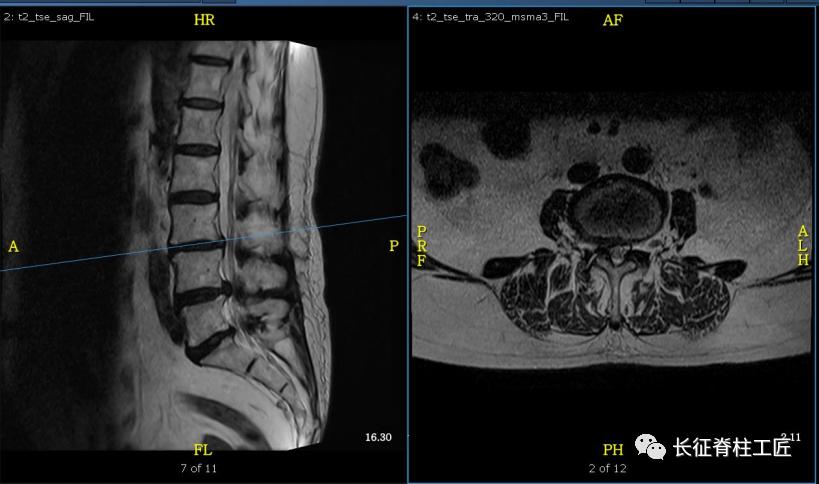

入院检查,腰部疼痛,后伸时加剧,局部压痛,双下肢肌力减退。X线检查,L4、L5骨质增生,MRI显示L4/L5、L5/S1椎间盘突出,马尾神经受压明显,被确诊为腰椎管狭窄症。

腰椎管是由前方的椎体后壁、椎间盘,侧方的椎弓根和关节突以及韧带,后方的椎板和黄韧带组成。这些组成部分增生肥厚或者椎间盘的突出,都可以造成中央椎管、神经根管或椎间孔处狭窄。